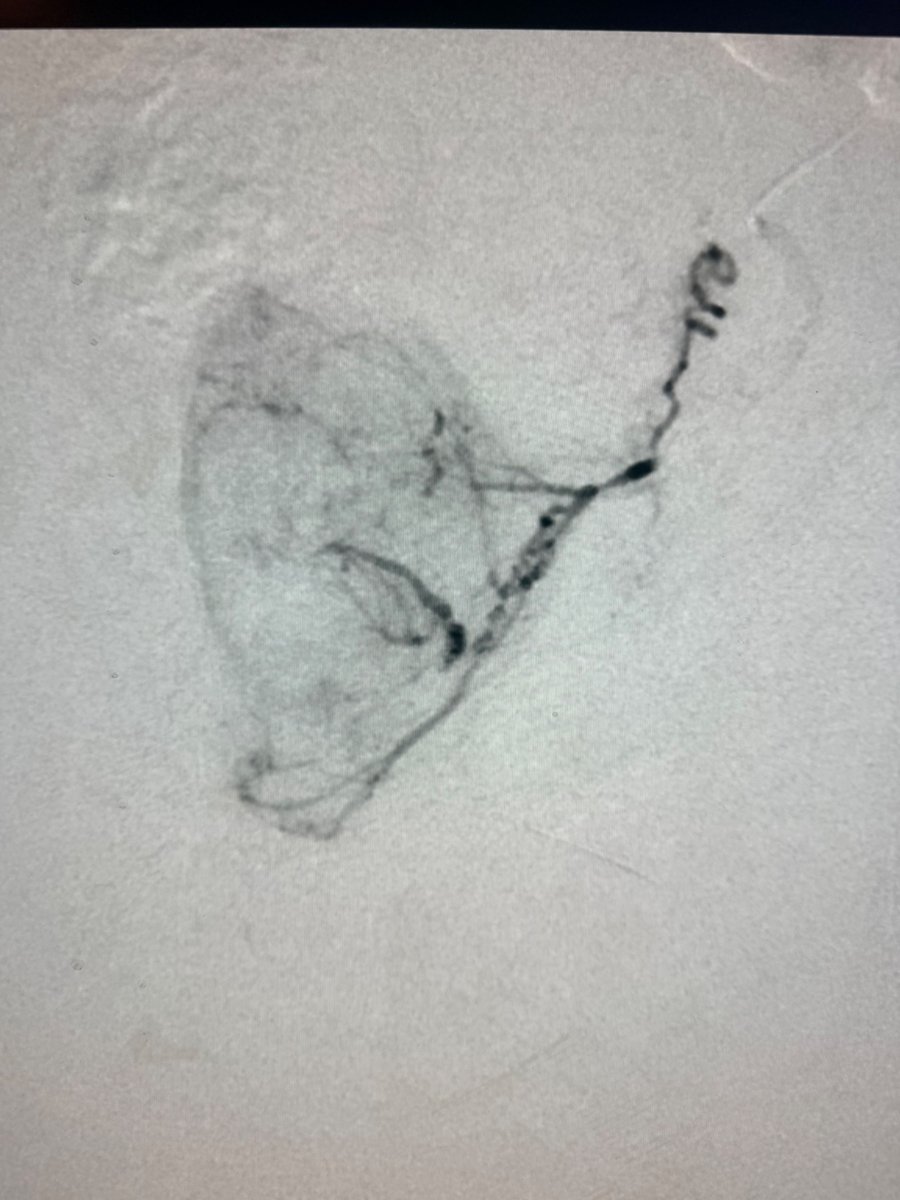

Dr. Kim published a case report in the Journal of Vascular & Interventional Radiology detailing a unique prostate artery embolization procedure. The report highlights the clinical approach & outcomes of this minimally invasive treatment for BPH. @DrGluRu jvir.org/article/S1051-…